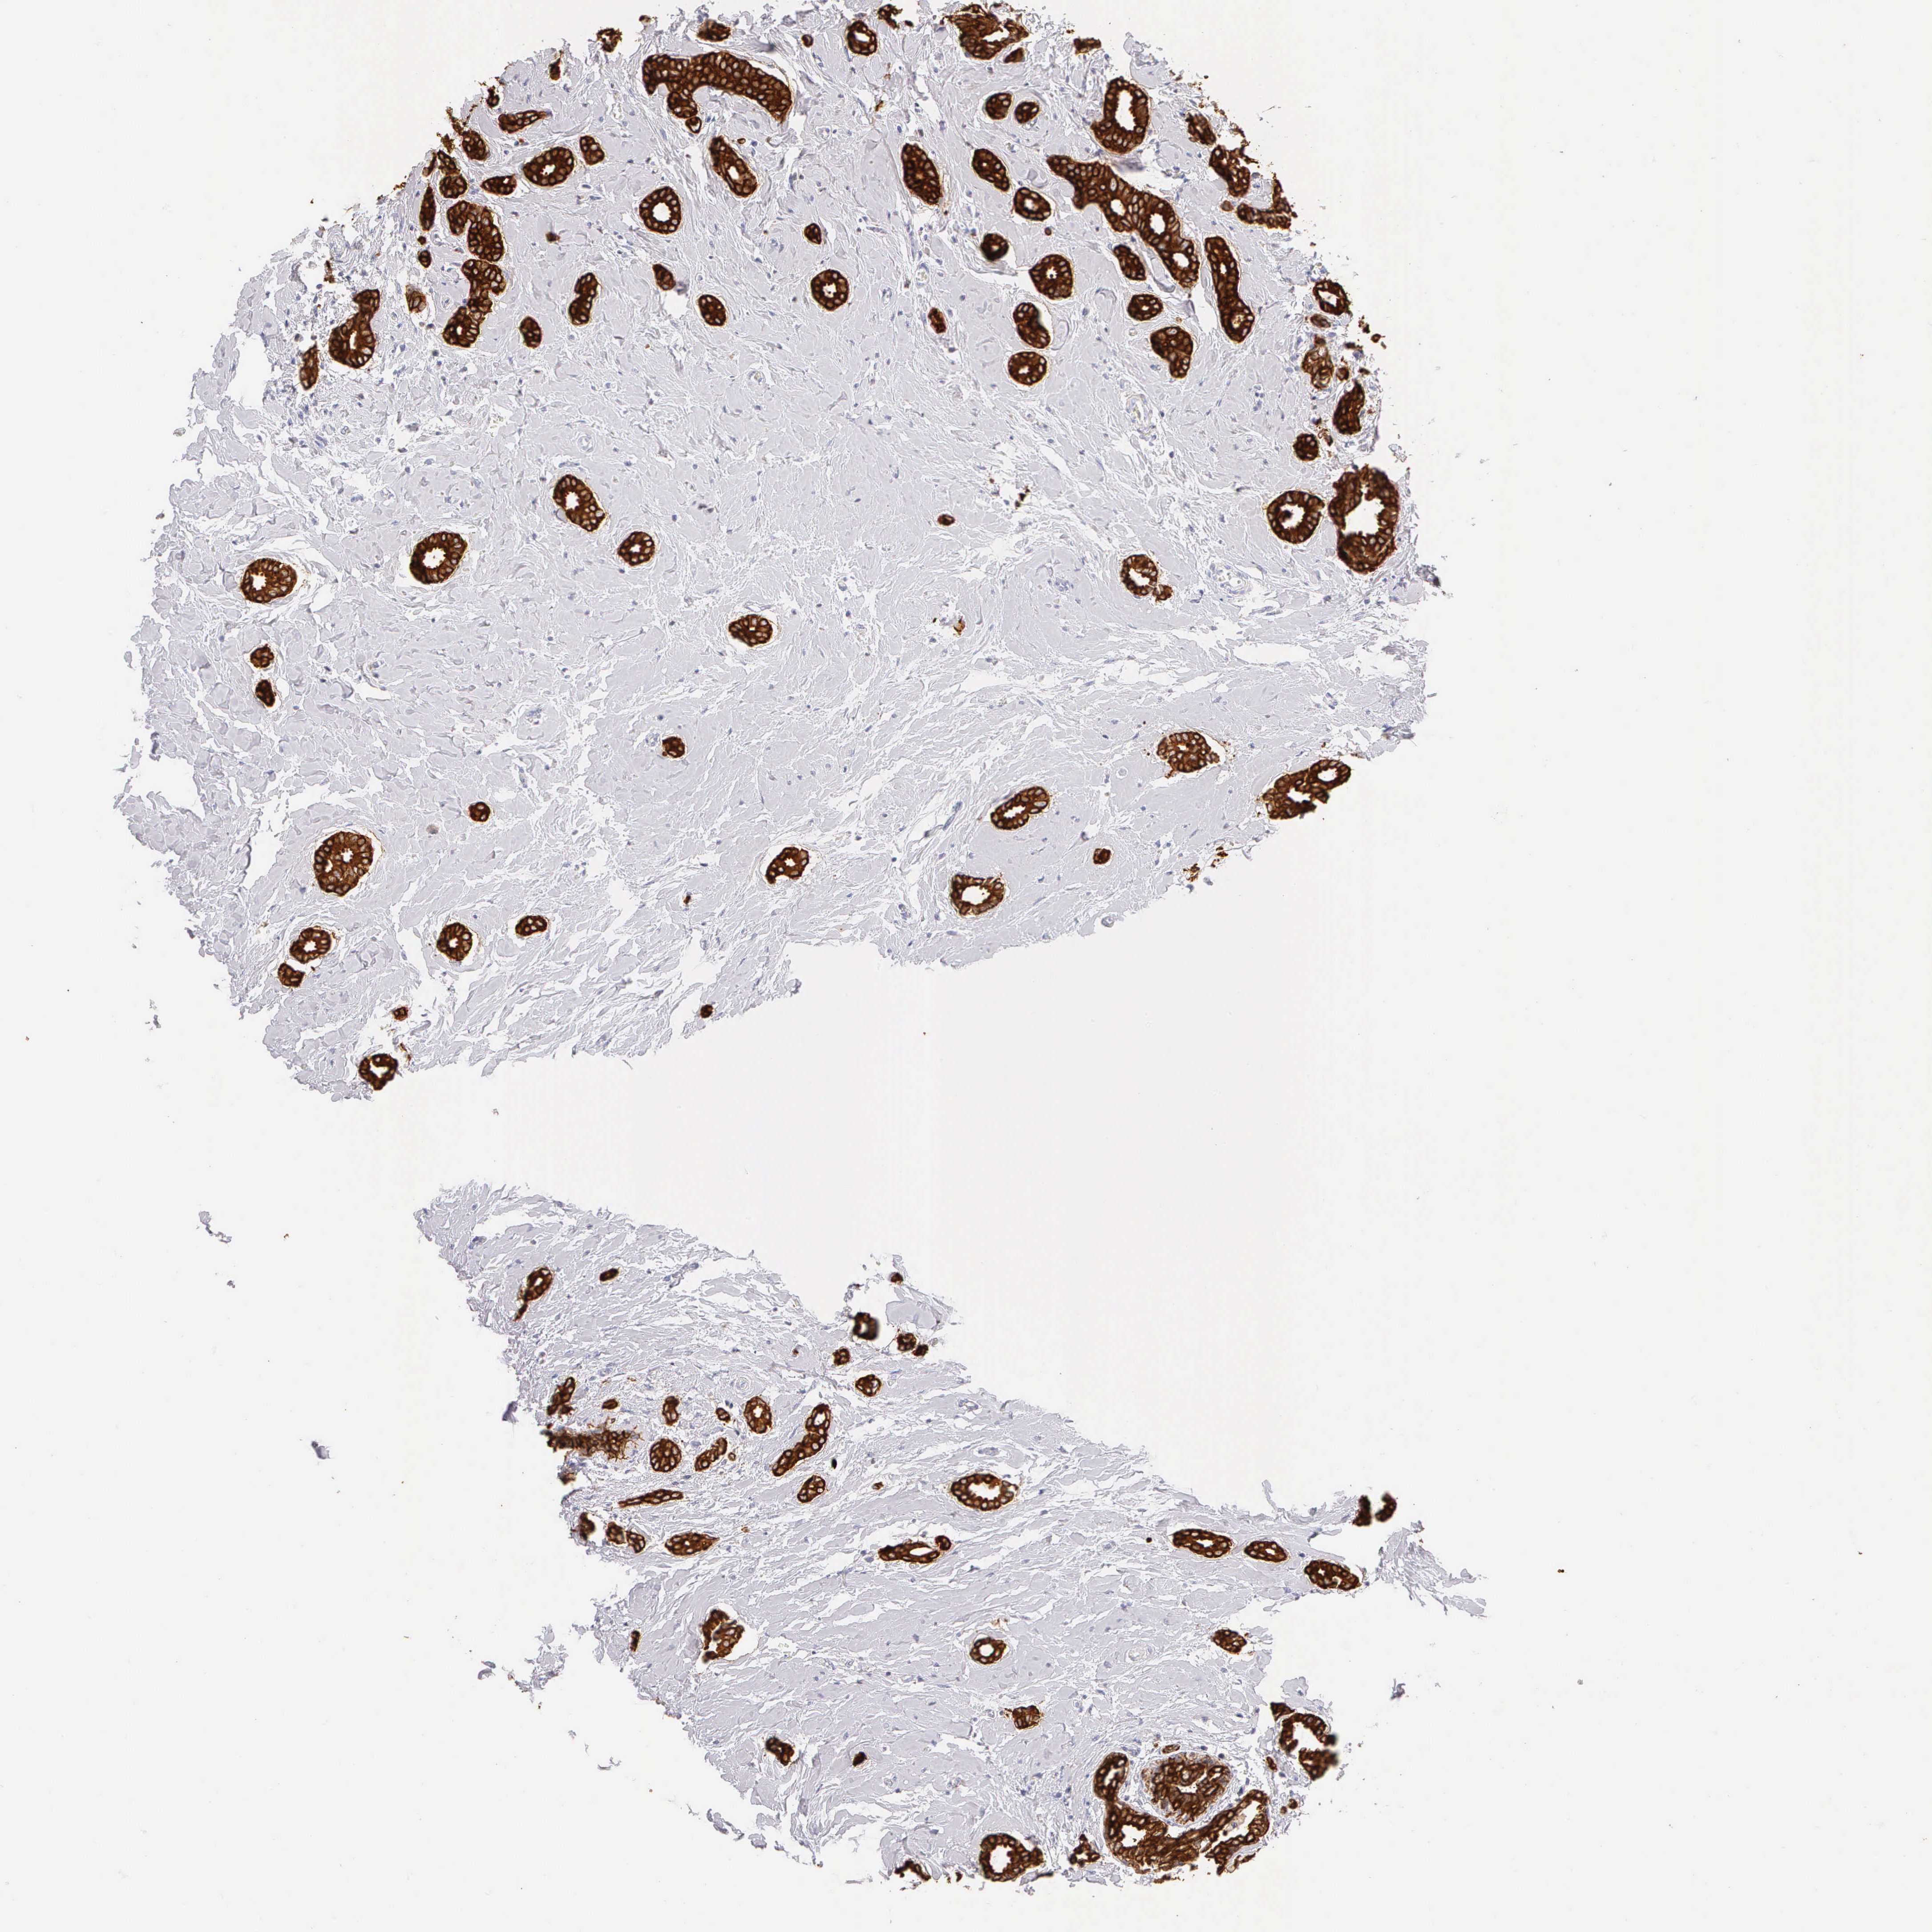

CANCER BREAST CANCER Show tissue menu

BRCA TCGA BRCA VALIDATION PROTEIN EXPRESSION

Breast cancer

Human cancer